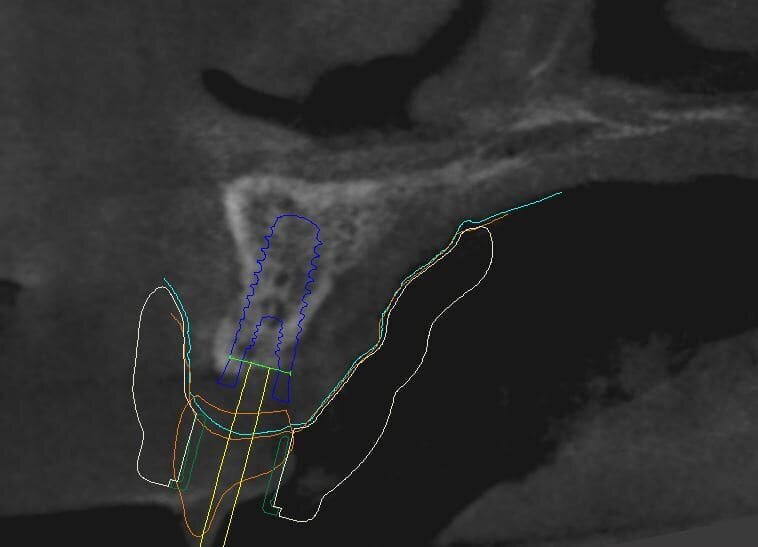

Fig. 10_La visione ingrandita del sito implantare esalta alcuni elementi che hanno contribuito nella scelta della posizione, dei materiali e della tecnica chirurgica esecutiva. Si nota Ion bianco il margine della dima chirurgica, in verde il profilo mucoso, in arancio la forma in sezione assiale della corona protesica in blu il contorno dell’impianto in Zirconia pure Ceramic e in giallo in tragitto di connessione che consentirà l’avvitamento della corona finale.

Fig. 11_Il dettaglio descritto dalla visione laterale con in bianco la forma della dima chirurgica in giallo il wax-up in rosso l’impianto in Zirconia e in verde la sleeve, cioè la cannula, che verrà posizionata nella dima per il passaggio delle frese calibrate e supportate da appositi supporti calibrati. È evidente la possibilità di far cadere nella porzione palatale il foro per l’avvitamento delle corone.